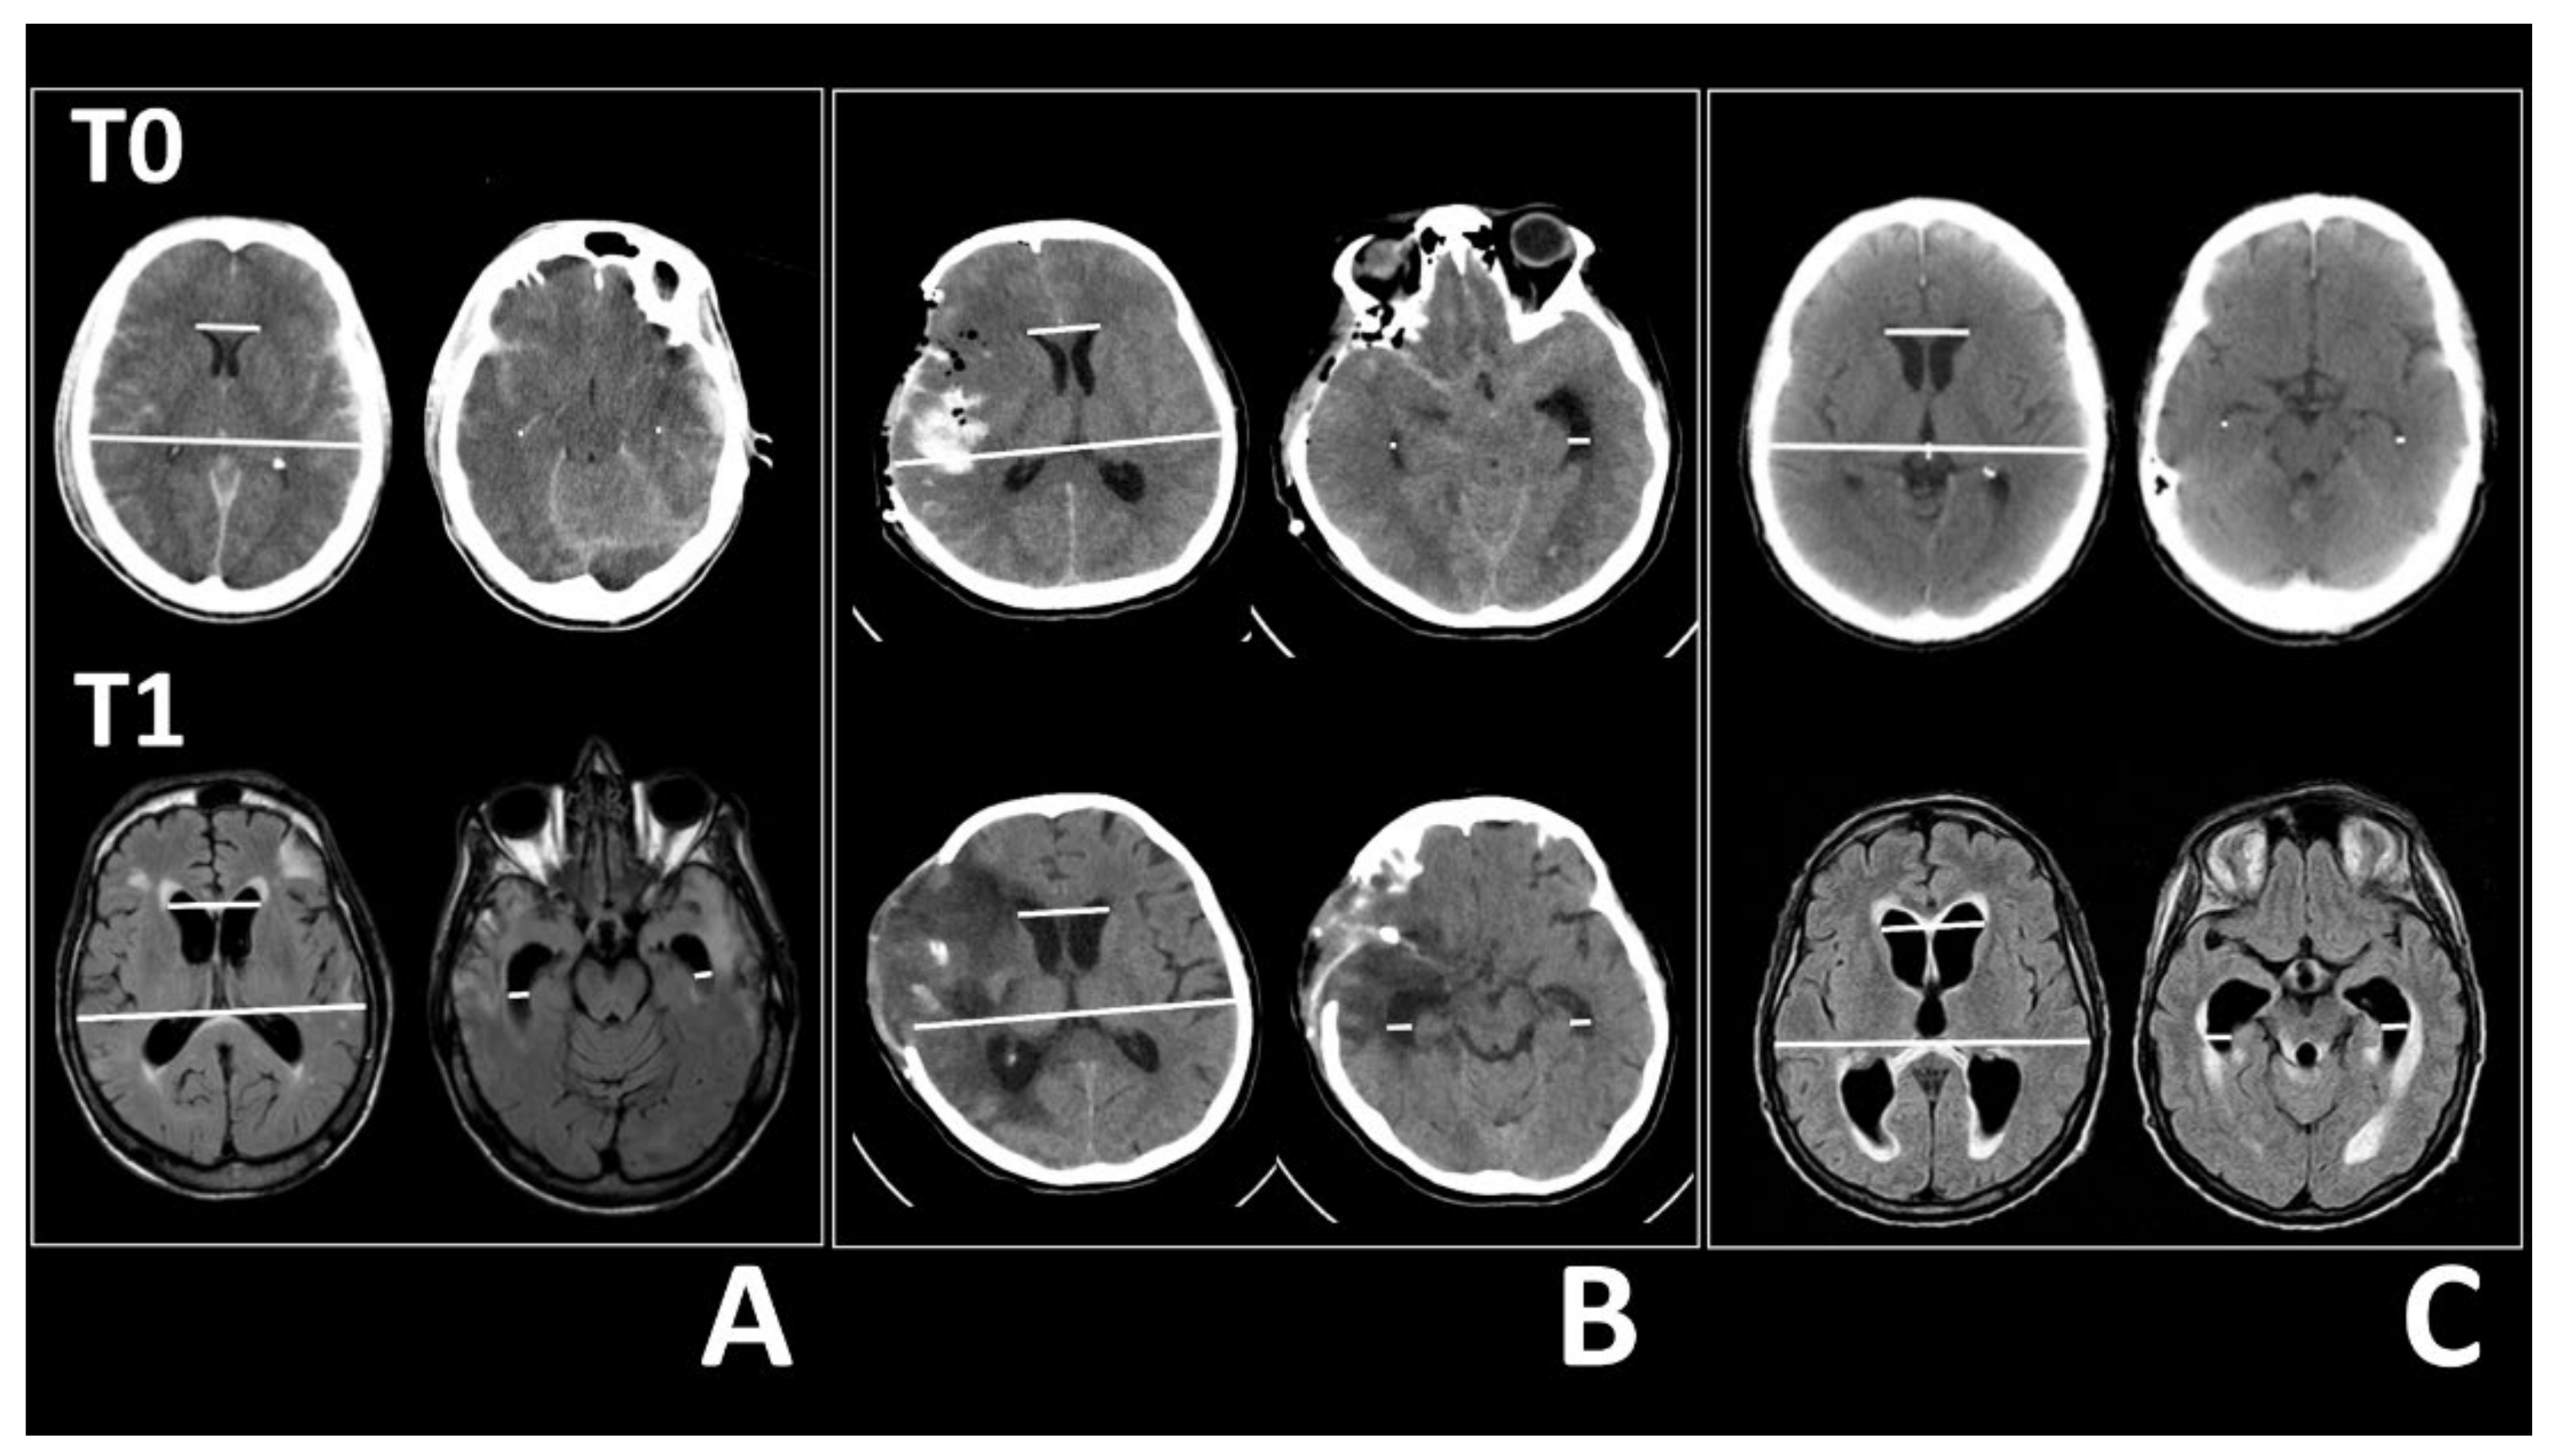

Figure 1. Images of CTs and MRIs acquired at admission (T0, top row) and at the first sign of ventricular enlargement (T1, bottom row) in three patients. (A) TBI patient, (B) SAH patient, (C) BT patient. In each panel, left images show the frontal horn distances and Evans’ index measurements (white lines), and right images show the temporal horn width measurements (white lines). (A) Compared to the CT images (T0), the MRI scans after 8 weeks (T1) shows that the frontal horns enlarged from 29.1 to 39.2 mm and the Evans’ index increased from 0.22 to 0.3 (left). The right temporal horn enlarged from 1.4 to 7.7 mm and the left temporal horn enlarged from 0.9 to 7.3 mm (right). (B) T0 image is scanned after clipping a middle right cerebral artery aneurysm and performing a decompressive craniectomy for SAH. A CT image acquired 19 days after surgery (T1) shows that the frontal horn distance enlarged from 30.1 to 37.7 mm and Evans’ index increased from 0.22 to 0.28 (left). The right temporal horn width enlarged from 1.9 to 9.1 mm and the left temporal horn width enlarged from 7.7 to 8.2 mm (right). (C) T0 CT scan shows a patient with fourth ventricle lymphoma. After 3 weeks (T1), the MRI shows an enlarged frontal horn distance (from 33.6 to 43.5 mm) and an increase in Evans’ index, from 0.25 to 0.32 (left). The right temporal horn width enlarged from 1.3 to 10.9 mm and the left temporal horn width enlarged from 1.7 to 11.4 mm (right).

Two independent observers (one neuroradiologist and one neurosurgeon with long neurosurgical experience on secondary hydrocephalus and its surgical treatment) examined axial scans and calculated Evans’ index, the bifrontal horn distance, which had been used to calculate Evans’ index, and the widths of the right and left temporal horns, strictly measured at the level of the ventricular prominence of the hippocampus (Figure 1). Agreement between observer measures was evaluated with the Kappa statistic. The percentage change from T0 to T1 was calculated for each measure (M) with the formula: (MT1 − MT0)/MT0 × 100%.